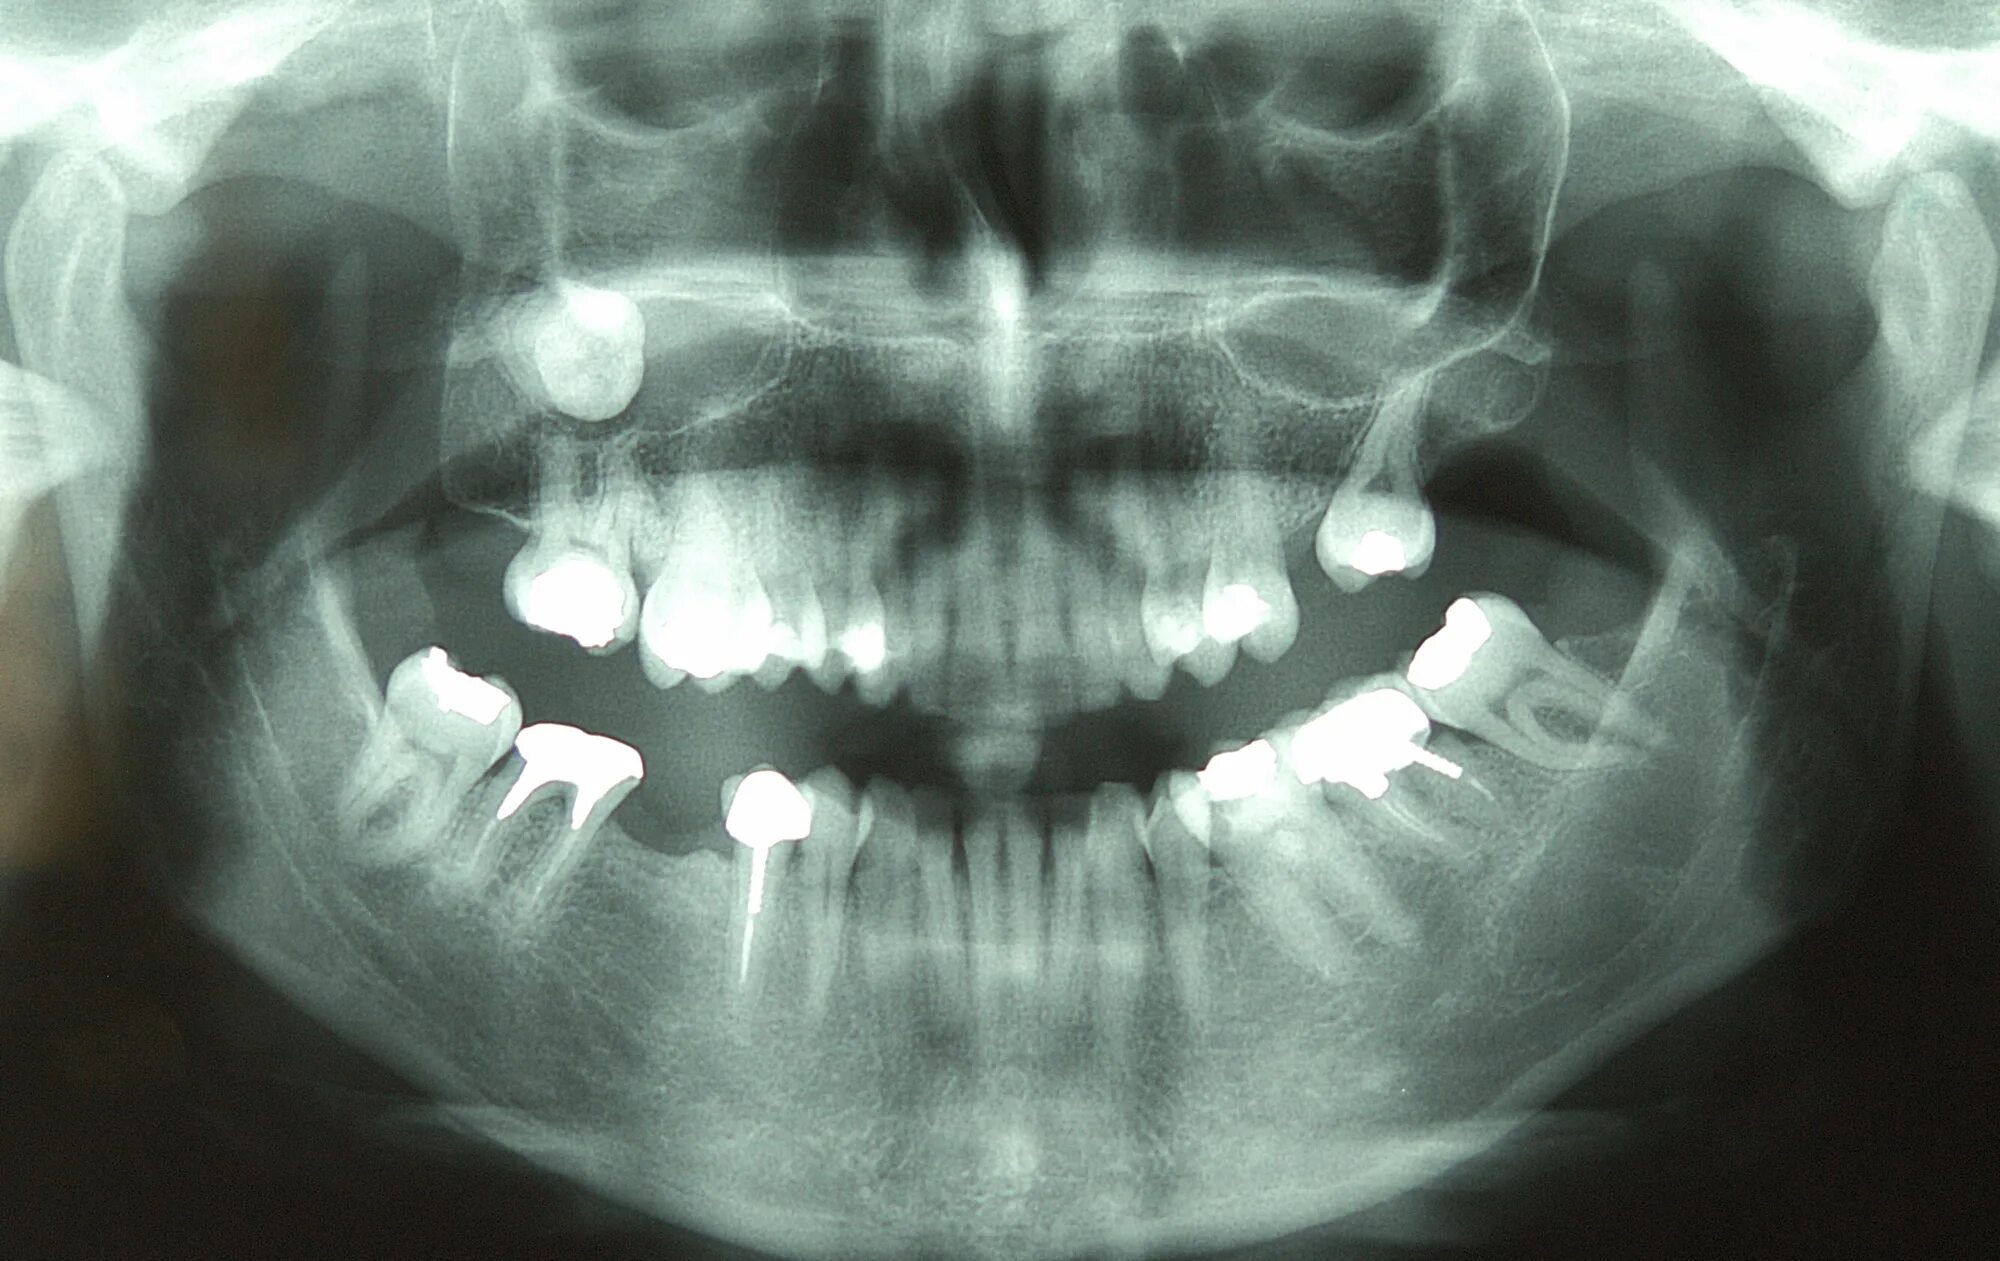

Киста зуба что это